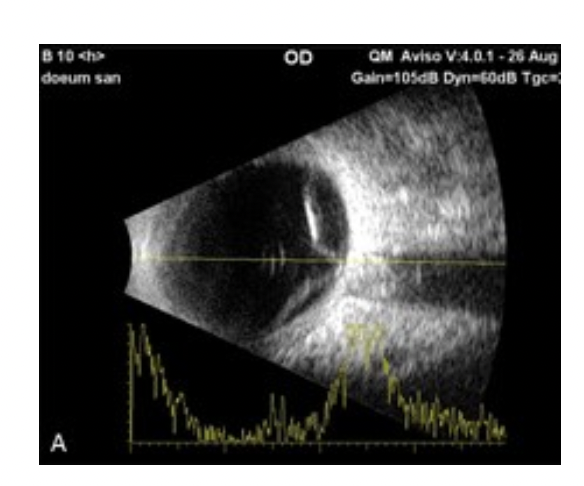

56-årig mand med tæt glaslegemeblødning på højre øje.

Du foretager en ultralydsskanning af øjet og får flg. billede på højre øje;

Hvilken diagnose mistænker du nu og hvilken behandling vil du tilråde patienten?

- Du mistænker at patienten har amotio retina og tilråder ham en hurtig vitrektomi (intern

amotiooperation). - Skanningen giver mistanke til våde AMD-forandringer og patienten tilrådes anti-VEGF

behandling. - Glaslegemesammenfaldet har medført en glaslegemeblødning. Patienten tilrådes en ny

kontrol om 1 uge, da en sådan blødning ofte forsvinder af sig selv uden behandling. - Patienten tilrådes retinal fotokoagulation, da det formentlig er et retinalt hul, som har

forårsaget forandringerne.

- Du mistænker at patienten har amotio retina og tilråder ham en hurtig vitrektomi (intern

amotiooperation) .